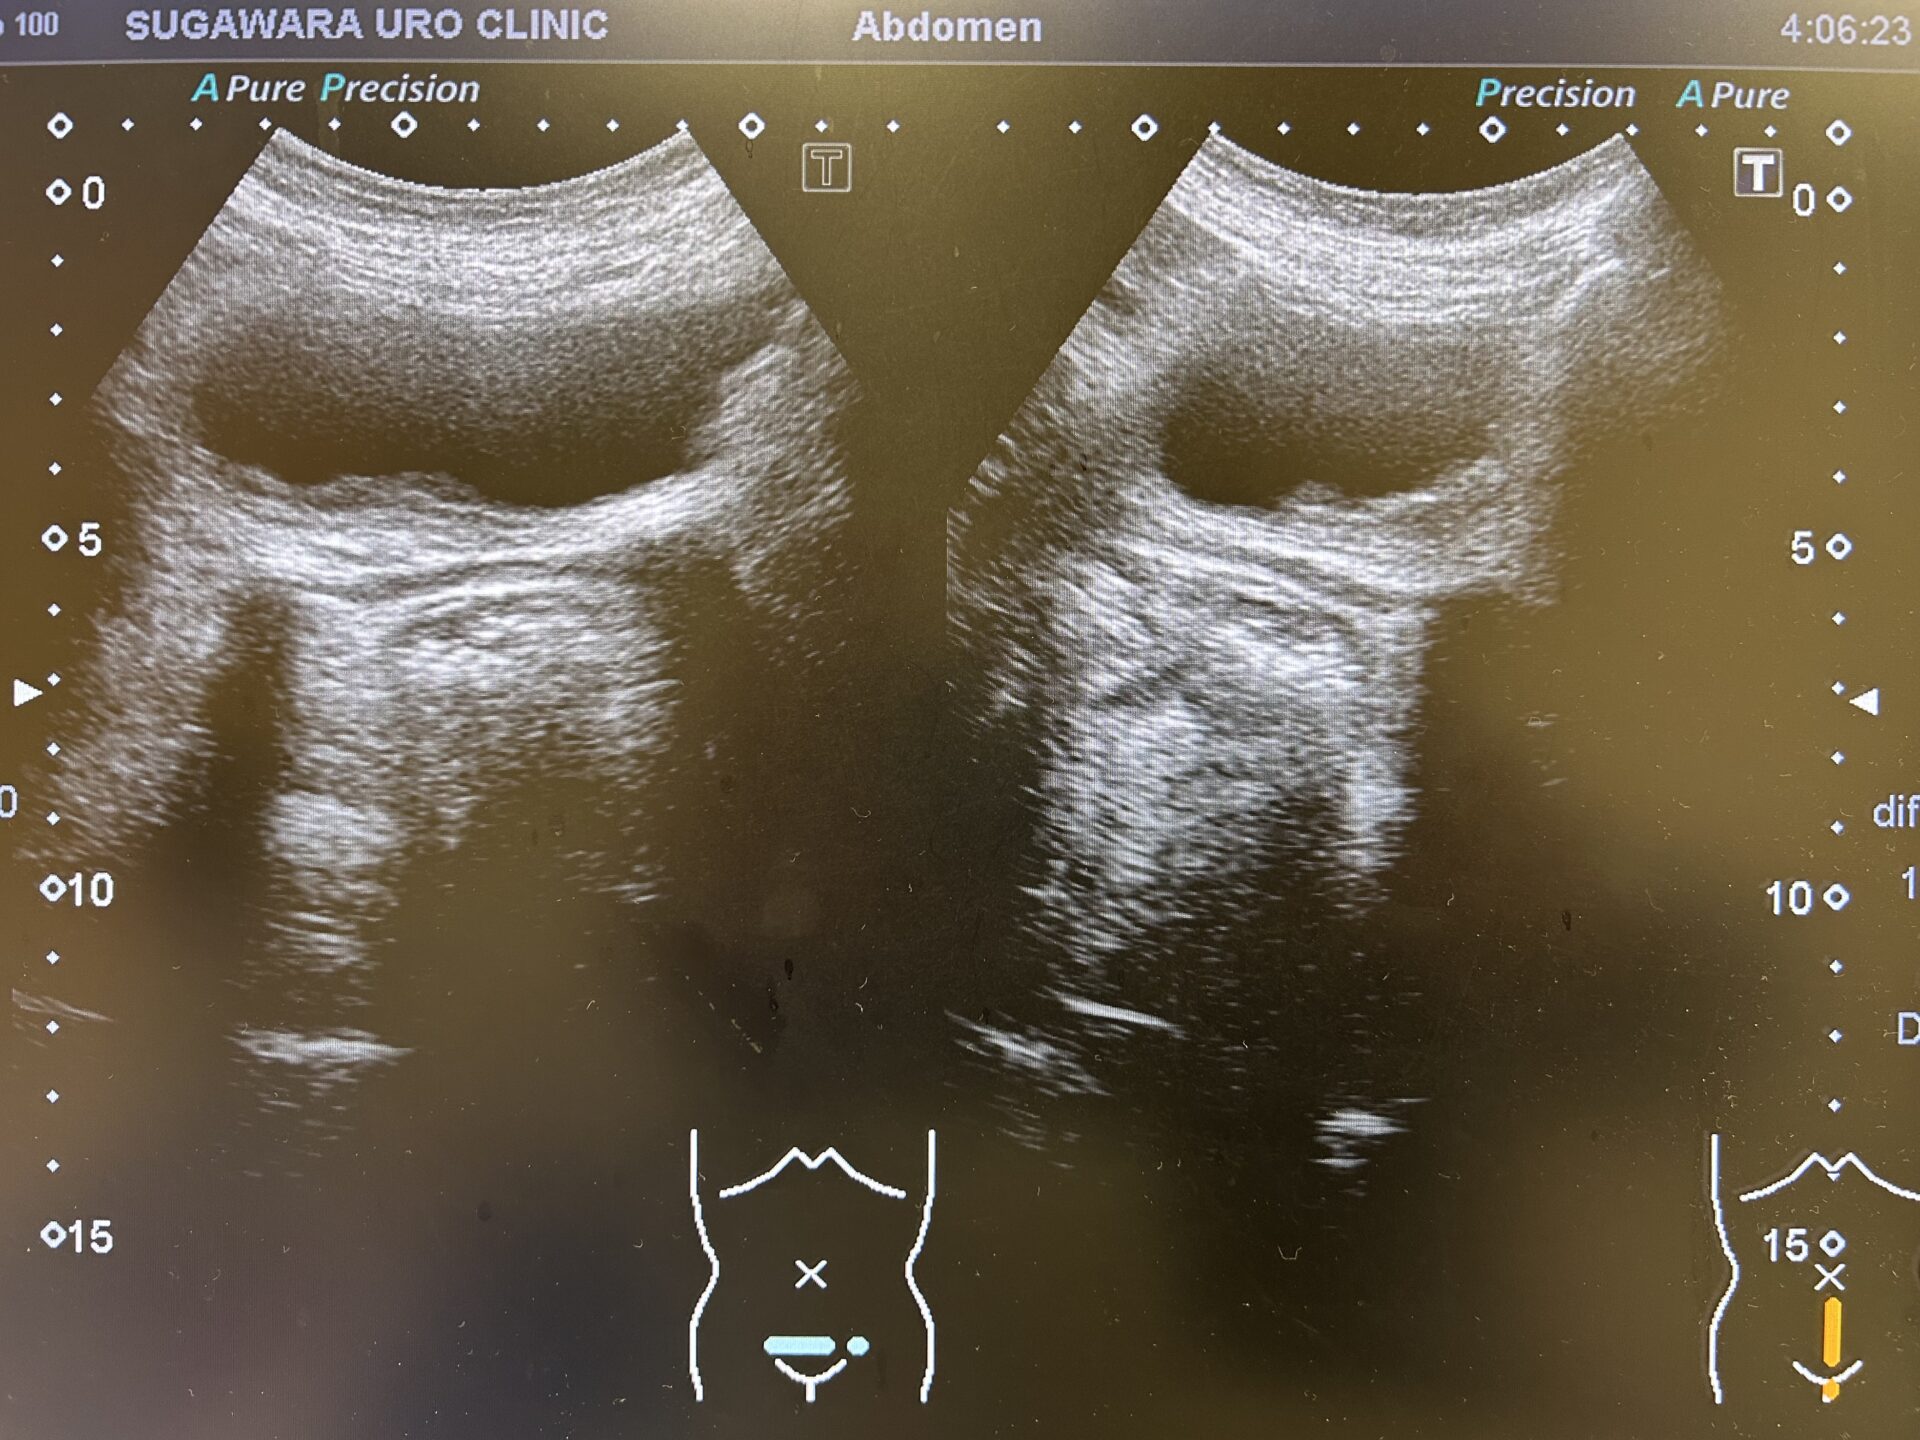

【半年前には右水腎症は認められていなかった】